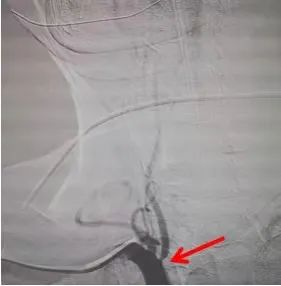

患者,男,65岁,因“头晕、饮水呛咳”入院,核磁检查提示右侧延髓、小脑半球梗死,头颈部CTA检查提示右椎动脉开口重度狭窄,考虑为本次脑梗死责任血管,为进一步防范更严重脑卒中发生,于住院1周后经桡动脉途径顺利行右椎动脉支架植入术。术后患者病情稳定,头晕好转,饮水稍呛咳,吞咽水试验2级,四肢活动正常,住院12天后顺利出院。

经桡动脉术前造影提示右椎开口重度狭窄